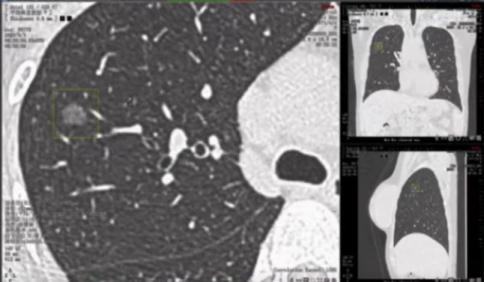

患者,女,49岁,既往无吸烟史;CT发现双肺小结节1年,为进一步明确诊断进行薄层CT扫描并将影像学资料交与AI进行进一步判定。

AI判读发现患者右上肺有10.8*8.5 mm结节,且在左肺见7.2*5.3 mm结节。两结节均呈现空泡征且有新生血管生成,左肺结节更是存在分叶征。

最初发现右肺结节时,由于结节较小判读比较困难,医生并没有给出明确诊断而时嘱托患者继续随访。本次患者影像学经AI评估,认为患者右上肺结节可能高度恶性可疑,左下肺结节恶性风险稍低但依然存在。